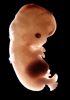

Carnegie Stage 22 (54 post-ovulatory days)

Most embryos at stage 22 are approximately 54 postovulatory days old and measure 25-27 mm in length. Distinguishing criteria for this stage include clear formation of the external ear, the hands begin to extend ventrally beyond the body wall, the fingers of one hand may overlap the fingers of the opposite hand, thickened eyelids just begin to cover the outer margins of the eye, and the superficial vascular plexus of the head now extends about three-quarters of the way above the eye-ear level.

Photographs